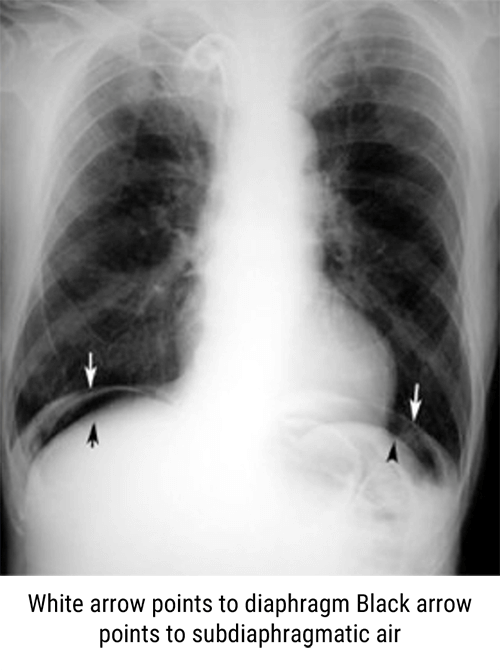

However, intestinal perforations, air fluid levels and obstructions are detected on an upright abdomen when compared to a supine abdominal X-ray.

Pneumoperitoneum

The peritoneum is the serous membrane forming the lining of the abdominal cavity. It covers most of the intra-abdominal organs, and is composed of a layer of mesothelium supported by a thin layer of connective tissue.

Pneumoperitoneum describes gas within the peritoneal cavity, often due to critical illness. There are numerous causes of pneumoperitoneum. These include ischemic bowel, appendicitis, diverticulitis, malignancy, inflammatory bowel disease, necrotizing enterocolitis, and bowel obstructions.

The most common cause of pneumoperitoneum is from the disruption of the wall of a hollow viscus. It is important to know that causes for pneumoperitoneum in adults differ from those in children.

- Rated hollow viscus

- Peptic ulcer disease

- Ischemic bowel

- Bowel obstruction

- Necrotizing enterocolitis

- Appendicitis

- Diverticulitis

- And malignancy

Perform only the examinations requested by the physician. Keep in mind that an upright abdomen should be performed to include the diaphragm for the evaluation of intestinal perforation.